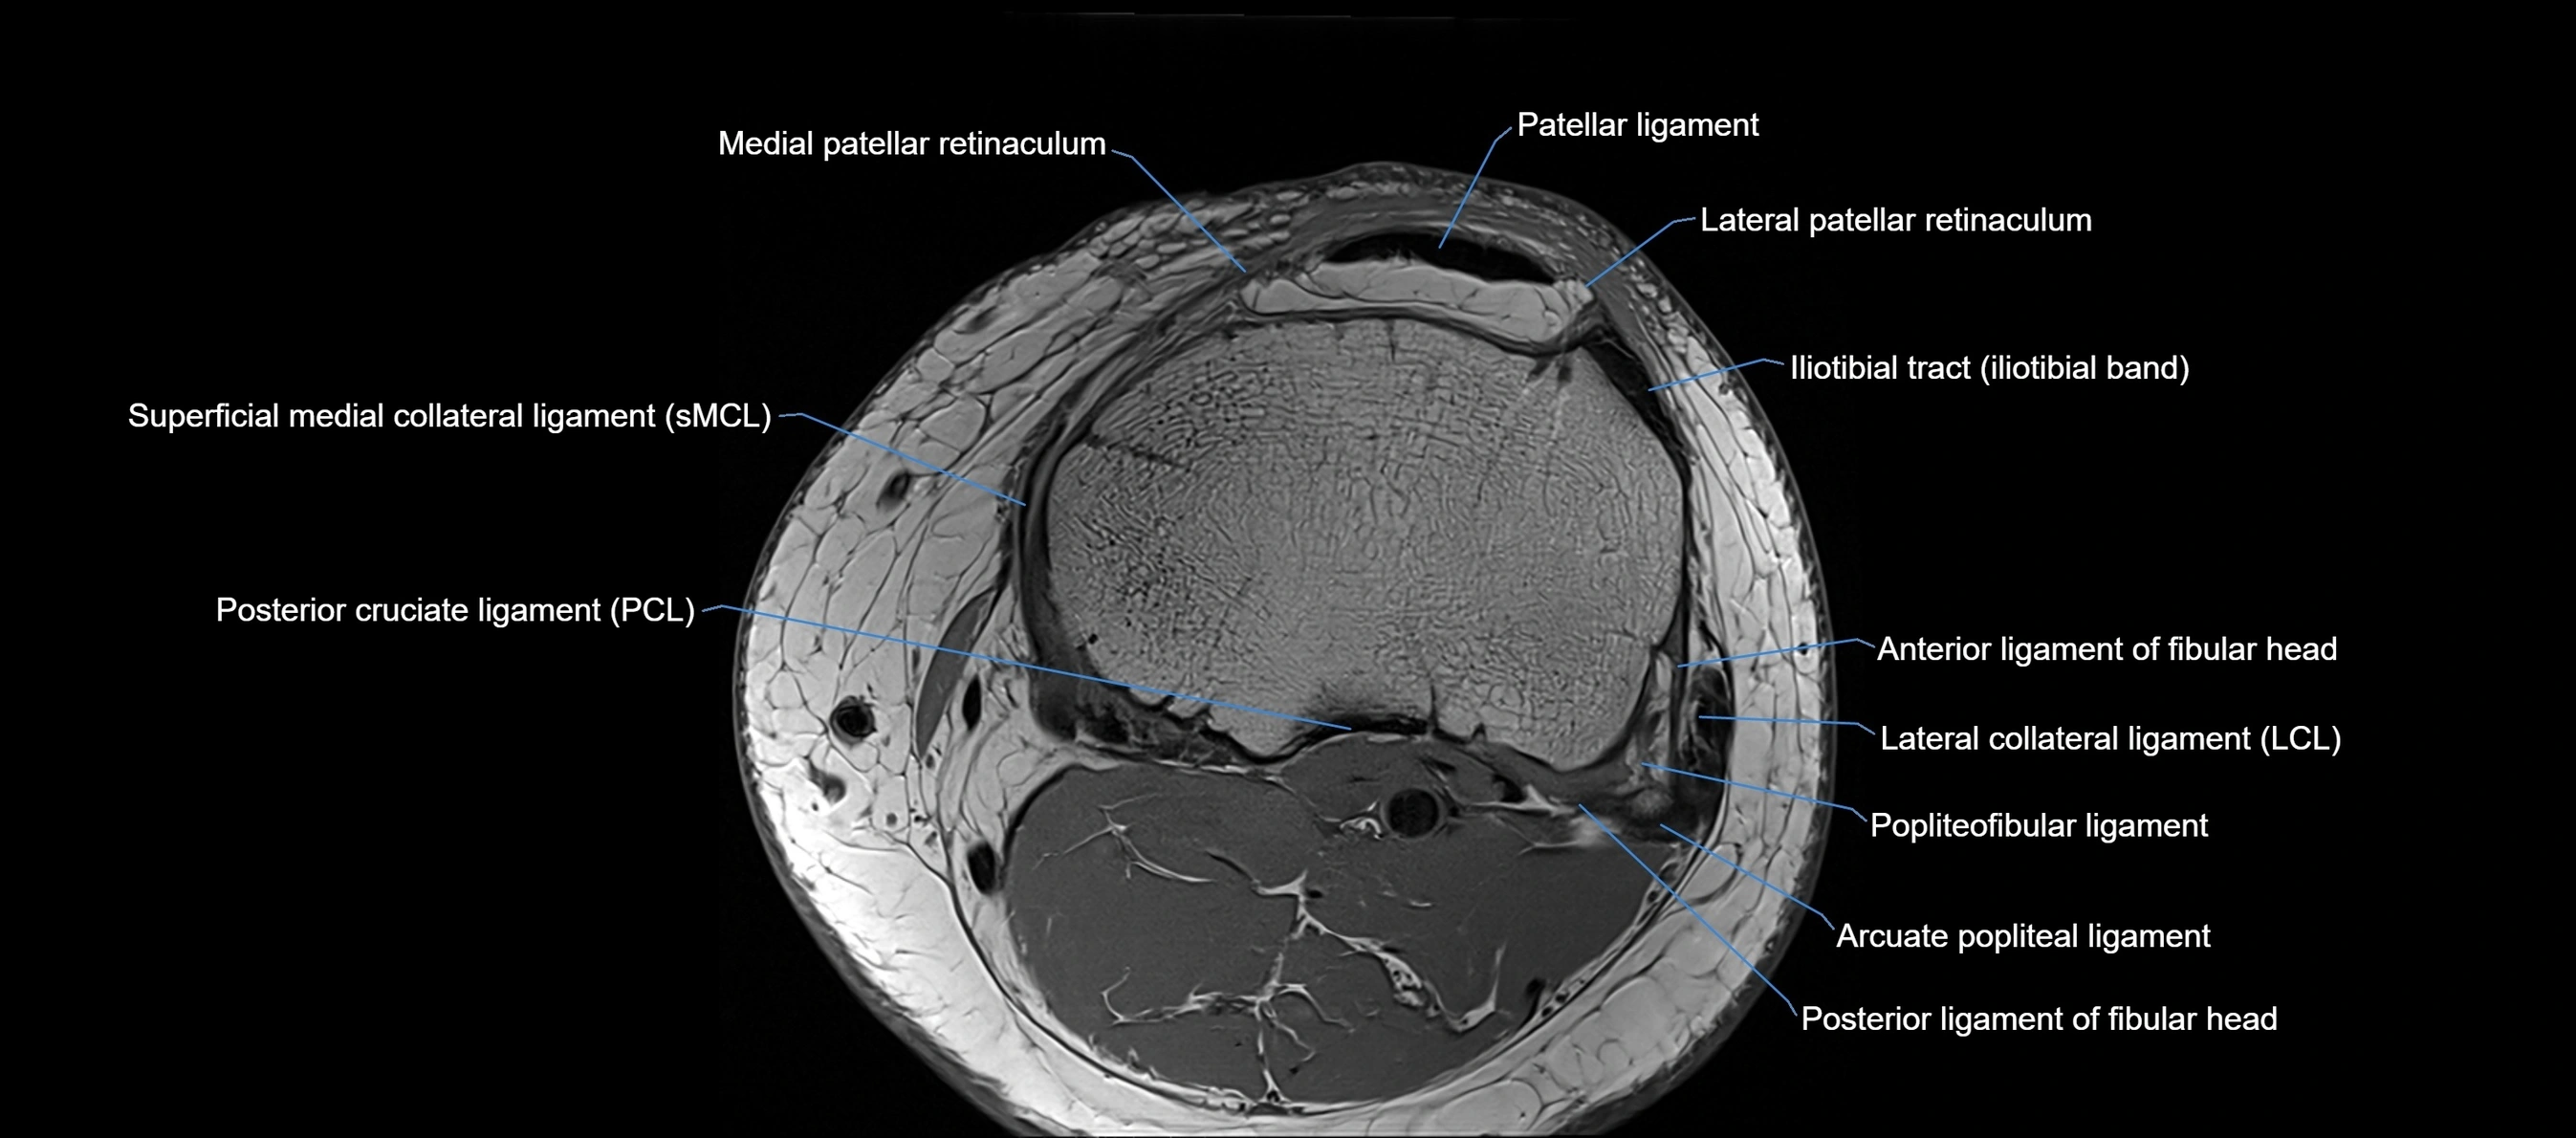

MRI images

image